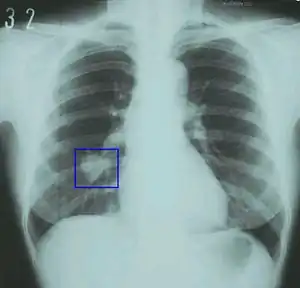

Tobacco smoking, most often associated with "coffin nails," or cigarettes of the tobacco plant (Nicotiana tabacum), is a foul, expensive, unhealthy habit that stains your fingers and teeth, costs a fortune, "harms nearly every organ of the body" and causes or increases the risks of a staggering amount of diseases below:[2]

- cancer of the lungs (most cases), and some cancers of the bladder, blood (acute myeloid leukemia), cervix, colon and rectum, esophagus, kidney and ureter, larynx, liver, oropharynx, pancreas, and stomach